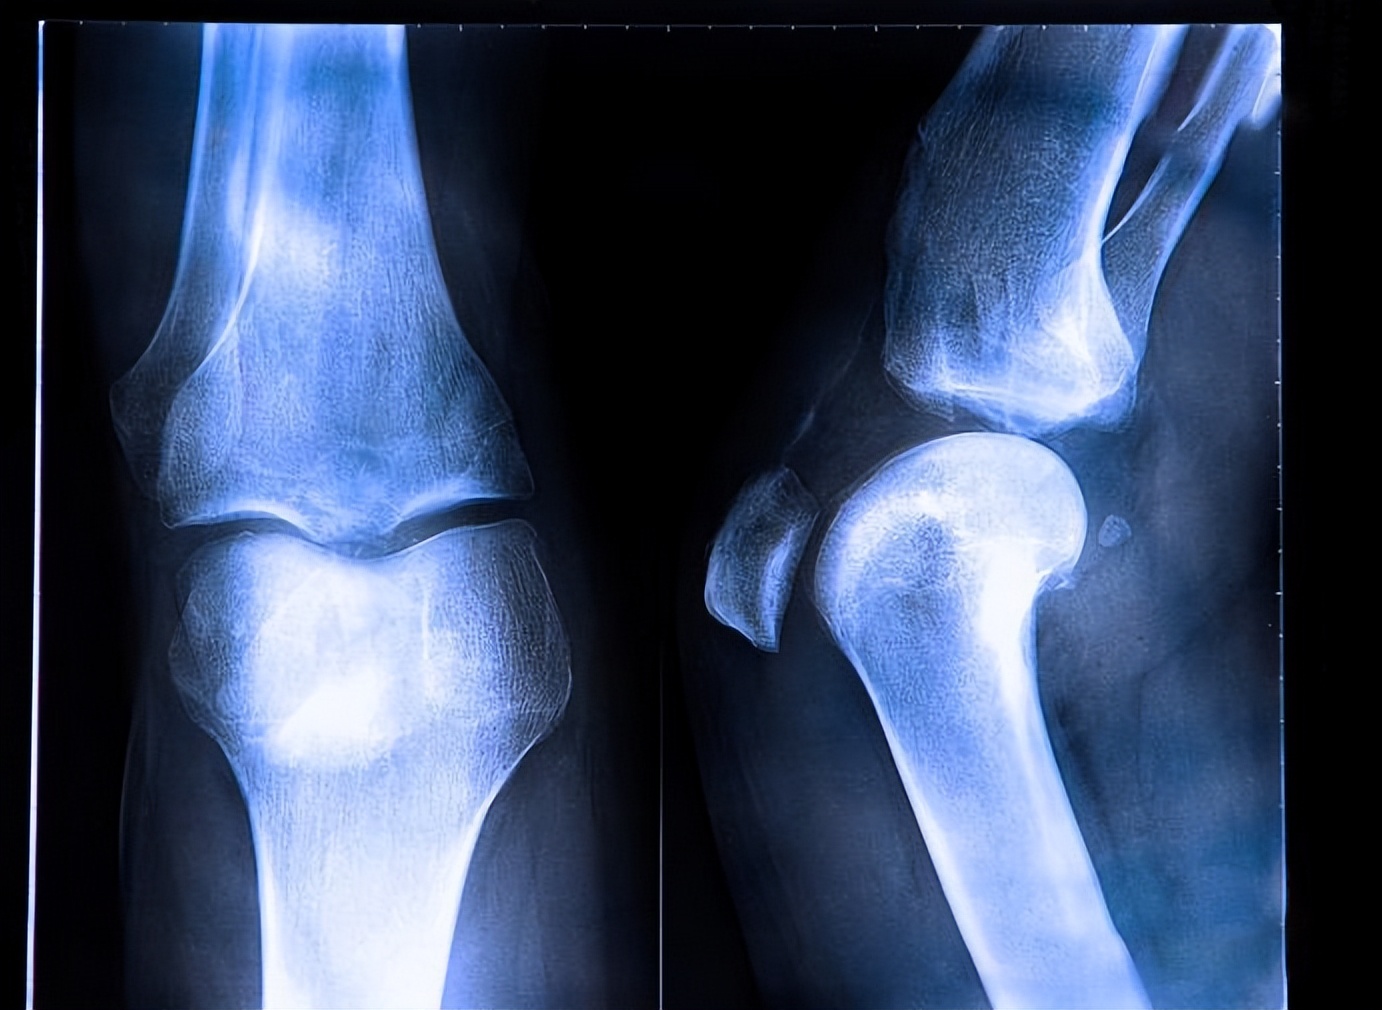

- X线检查:X线检查也可用于前交叉韧带(ACL)损伤的诊断。胫骨踝间棘骨折提示ACL胫骨附着部撕脱;骨折或外侧关节囊撕脱骨折是ACL撕裂的病理征象。